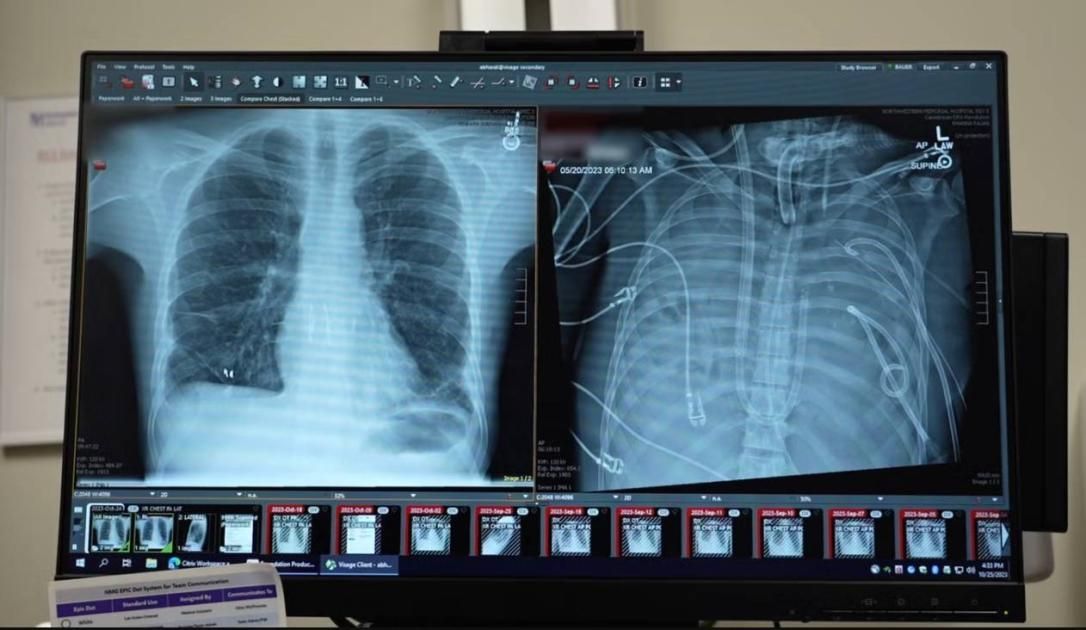

أنقذ جراحون أمريكيون من جامعة نورث وسترن بولاية إلينوي، حياة رجل يبلغ 33 عاماً بعد أن عاش يومين كاملين دون رئتين، باستخدام واحدة اصطناعية مؤقتة قبل إجراء عملية زرع اثنتين مزدوجتين.

أصيب الرجل بمتلازمة الضائقة التنفسية الحادة نتيجة التهاب إنفلونزا، ما تسبب في تدهور رئتيه بسرعة وإصابته بالتهاب رئوي بكتيري حاد، أدى في نهاية المطاف إلى فشل قلبه وكليتيه ورئتيه، وأصبح زرع الرئتين الخيار الوحيد لإنقاذ حياته.

وأضاف: كان جسم المريض أضعف من أن يقبل رئتين جديدتين ويحتاج إلى مزيد من الوقت للشفاء من الالتهاب، لذلك صممنا له رئة اصطناعية مؤقتة تقوم بوظائف الأكسجة وإزالة ثاني أكسيد الكربون، والحفاظ على استقرار تدفق الدم عبر الجسم حتى تتوفر رئتا المتبرع.

وتابع: بعد يومين، أصبحت رئتا المتبرع متاحتين وأجريت للمريض عملية زرع رئة مزدوجة بنجاح وعاد إلى حياته اليومية بوظائف رئوية طبيعية.